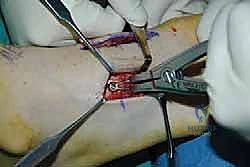

2. الشق الجراحي والوصول للمفاصل

يتم عمل شق جراحي واحد أو شقين (أحدهما في الجزء العلوي الداخلي والآخر في الجزء الخارجي) للوصول إلى مفاصل منتصف القدم دون الإضرار بالأوتار الحيوية والأعصاب والأوعية الدموية. يتم استخدام تقنيات الجراحة الدقيقة (Microsurgery) للحفاظ على الأنسجة المحيطة السليمة.

3. إزالة الغضاريف التالفة (Joint Preparation)

هذه هي الخطوة الأهم. يقوم الجراح بكحت وإزالة جميع الغضاريف المريضة والتالفة من بين العظام المراد دمجها. يجب الوصول إلى العظم الإسفنجي الصحي (Cancellous bone) الذي ينزف دماً، لأن هذا الدم يحتوي على الخلايا الجذعية وعوامل النمو الضرورية لعملية الالتحام (Fusion).